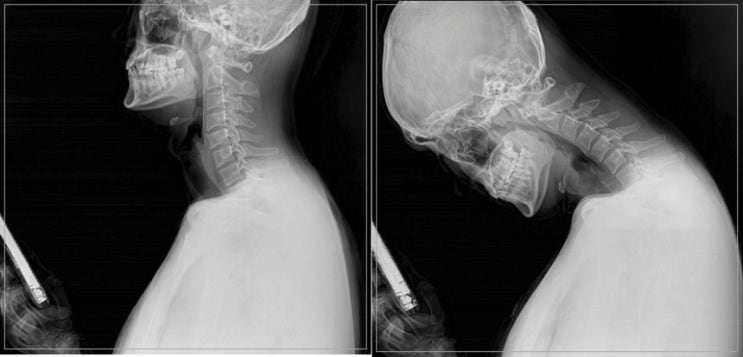

목 디스크를 예방하기 위해서는 무엇보다 바른 자세가 중요하다.

목 디스크 예방하려면 목 디스크를 예방하기 위해서는 무엇보다 바른 자세가 중요하다. 귀와 어깨선이 일치...